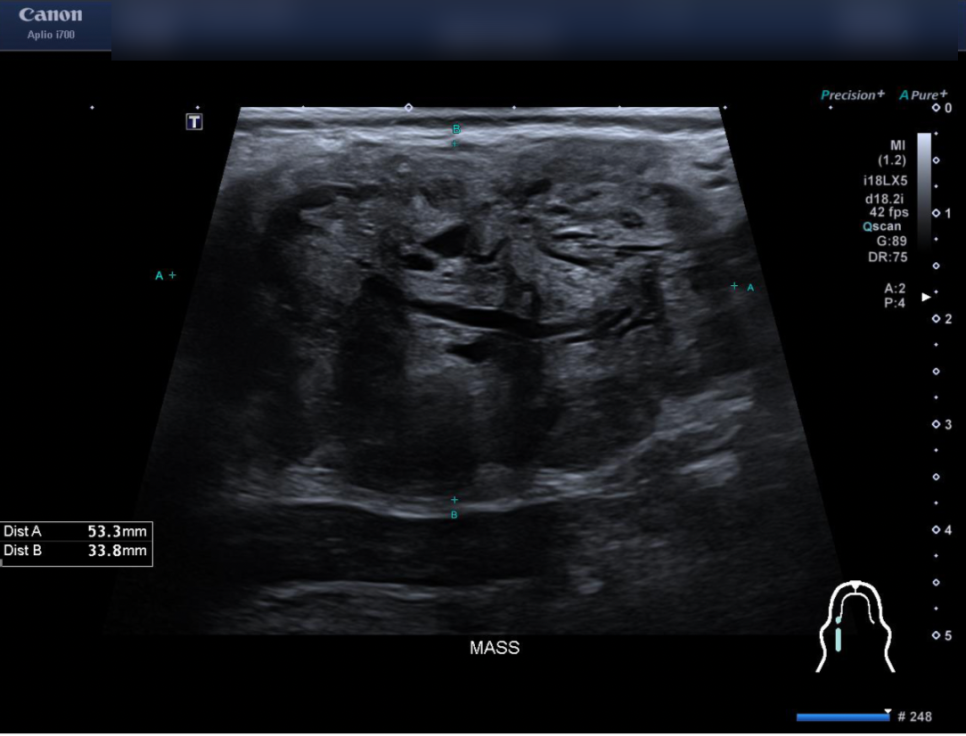

갑상선 종양 방사선 치료 후 초음파 사진 / 출처: 에스동물암센터

치료 종료 시점의 초음파 검사에서 종양 크기가 감소한 것이 확인되었으며, 추가적인 원격 전이 소견은 발견되지 않았습니다. 또한 환자는 방사선 치료 종료 후 환자의 상태에 맞춰 표적 항암치료를 계획하였습니다.